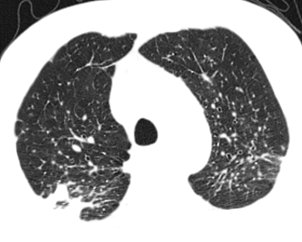

3. 继发性肺结核:继发性肺结核胸部影像表现多样。轻者主要表现为斑片、结节及索条影,或表现为结核瘤或孤立空洞;重者可表现为大叶性浸润、干酪性肺炎、多发空洞形成和支气管播散形成树芽征等;反复迁延进展者可出现肺损毁,损毁肺组织体积缩小,其内多发纤维厚壁空洞、继发性支气管扩张,或伴有多发钙化等,邻近肺门和纵隔结构牵拉移位,胸廓塌陷,胸膜增厚粘连,其他肺组织出现代偿性肺气肿和新旧不一的支气管播散病灶等。

*典型继发性肺结核:右上肺病变(上肺尖后段及下叶背段为结核好发部位),近心端空洞,可见引流支气管,周围可见播散灶(卫星灶)

*双上肺为主的多发空洞,痰抗酸染色阳性,实为非结核分枝杆菌肺病(胞内分枝杆菌肺病),误诊为肺结核

*典型右下叶背段沿支气管播散的树芽征,确诊为肺结核(但仍然需与其他支原体肺炎以及非结核分枝杆菌肺病鉴别)

*左上肺病变,具有多态性多灶性,误诊为肺结核,实为支原体肺炎(树雾征)

*表现为「反晕征」的肺结核,既往反晕征常描述为机化性肺炎、血管炎等特征性影像学表现,目前在肺结核中不少见。

*临床中尘肺误诊为肺结核非常常见,对于弥漫性病变一定强调职业史的询问

*空气新月征常作为曲霉菌特征性影像学表现,但肺结核也可以表现。此例患者为肺结核。